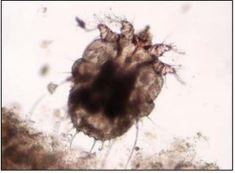

疥癬が疑われる場合には、皮膚の表面を専用の器具で強くこすり、皮膚の下に潜んでいるヒゼンダニを顕微鏡で確認することで診断します。

イヌセンコウヒゼンダニ